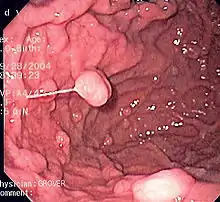

A series of radiographs can be used to examine the stomach for various disorders. This will often include the use of a barium swallow. Another method of examination of the stomach, is the use of an endoscope. A gastric emptying study is considered the gold standard to assess the gastric emptying rate.[43]

Human stomach

High-quality image of the stomach